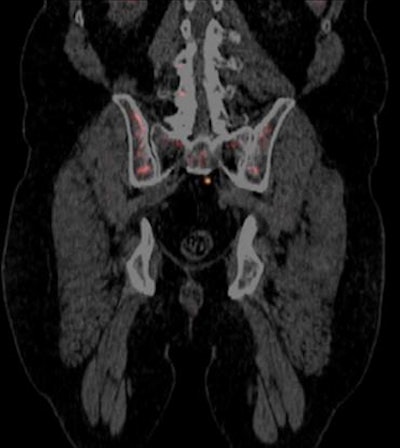

PET scan with Blue Earth's Axumin radiopharmaceutical. Image courtesy of Blue Earth Diagnostics.

PET scan with Blue Earth's Axumin radiopharmaceutical. Image courtesy of Blue Earth Diagnostics.In announcing the approval, the FDA noted that prostate cancer is the second-leading cause of cancer death in U.S. men. Accurate staging is key for managing patients who have a suspected recurrence of cancer after primary treatment.